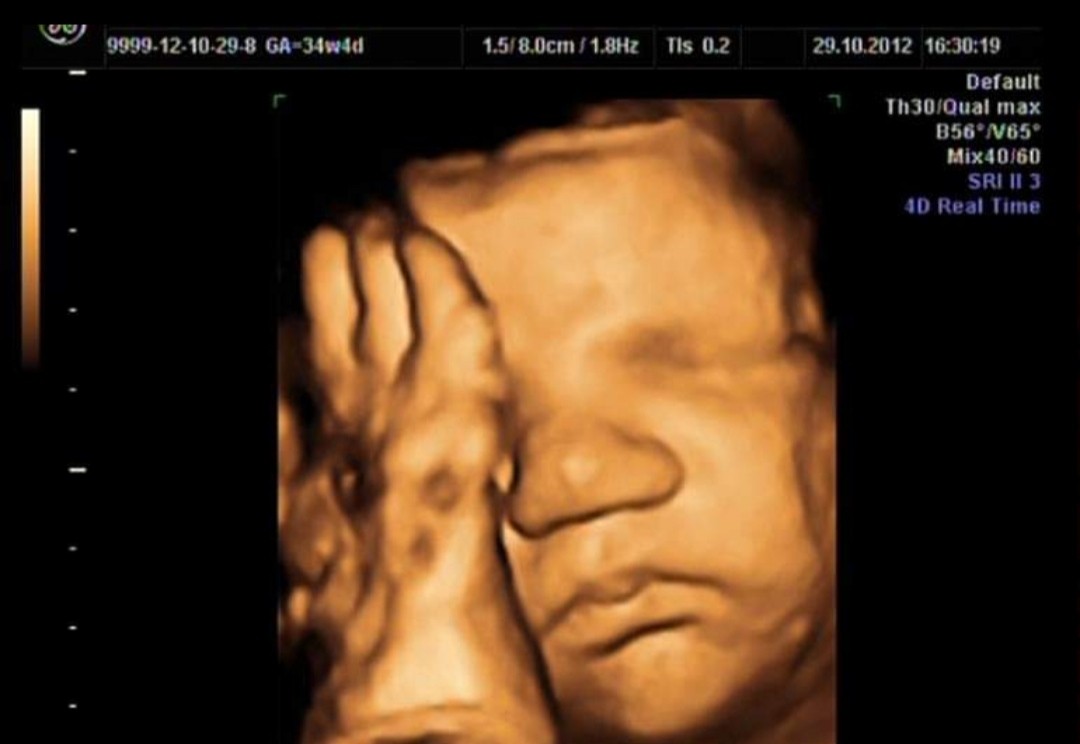

Nasze Maleństwo w piątek czyli jakies 8+3 miało 19mm.